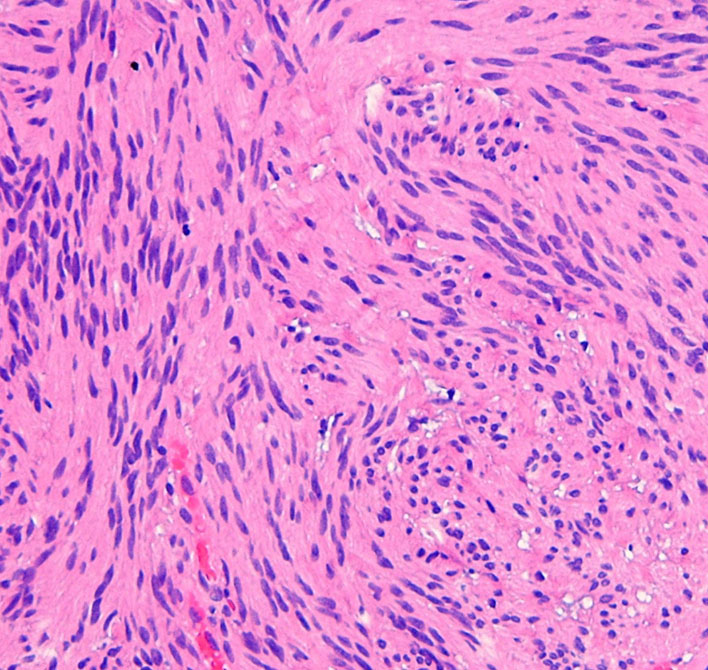

特殊な蔓状三叉神経鞘腫

NF-1ではない孤発例の三叉神経蔦状神経鞘腫です。眼窩内,上眼窩裂,メッケル腔,小脳橋角槽まで伸びる大きなものです。内視鏡の手術はできないので,開頭手術になりますが,全部まとめて摘出できます。